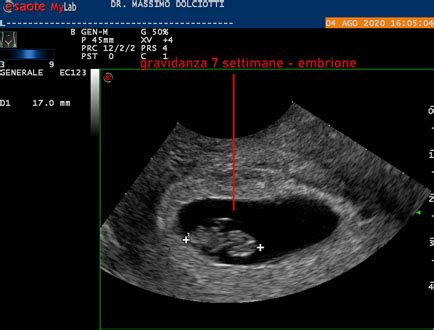

Dopo l'impianto, l'embrione subisce trasformazioni significative. Dal nono giorno nel sincizio-trofoblasto si sviluppano le lacune. Nel frattempo, il citotrofoblasto forma colonne di cellule che penetrano all'interno e sono circondate dal sincizio. Durante le prime 9 settimane di gravidanza si verificano una serie di trasformazioni significative nell’embrione e nel corpo materno. Nelle settimane 1-2, la blastocisti si impianta nell’endometrio e le cellule germinali primordiali iniziano a formare i precursori degli organi.